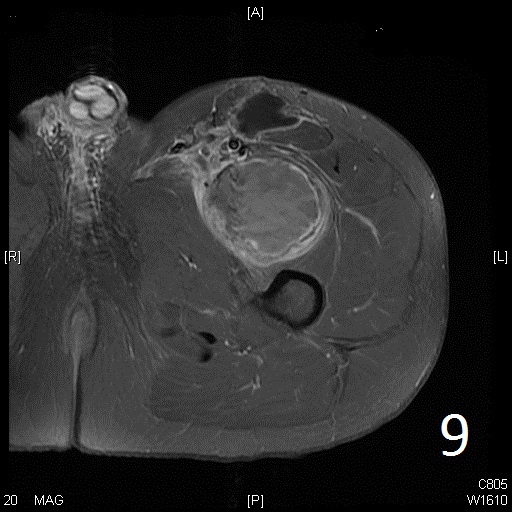

• 60% of fibrosarcomas are intramuscular (Fig. 2, 3, 5, 6, 7, 8)

• Well defined heterogenous mass on T2W (Fig. 4, 9)

• Necrosis and hemorrhage are common, especially in high grade tumors

• On gadolinium, viable areas of tumor enhance, while areas of significant necrosis and hemorrhage do not enhance (Fig. 6).

Fig. 5-9: Axial and sagittal (Fig. 6) MRI shows a fibrosarcoma in the proximal quadriceps muscle that is isointense to muscle on T1W images, and a heterogeneous on T2W FS (Fig. 7, 8). The patient was treated with preoperative chemotherapy and the mass underwent extensive necrosis. The mass does not show any enhancement with contrast due to the extensive necrosis. There is only peripheral enhancement with contrast on T1W FS (Fig. 9).